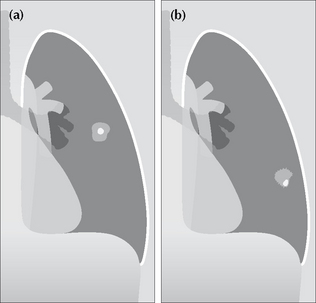

image

Figure 20.2 (a) Central calcification in a SPN is usually a benign feature. (b) Eccentric calcification raises the suspicion of a carcinoma arising in an old scar.